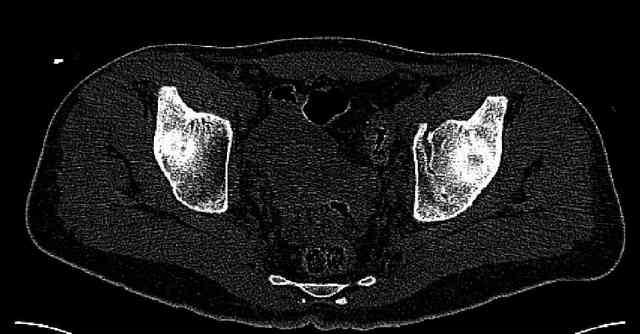

Some more images. Does it help to guess which part of the acetabulum is displaced?

Normal appearing SI joints and a healed posterior column limb... my bet's on caudal segment displacement.

While not claiming to have the best 3D brain around, it appears to me from the limited images available, that the caudal segment is stable from the symphysis to the SI joint on the fracture side. I would love to see the rest of the transverse CT images to see where the fracture line actually exits posteriorly on both the inner and outer tables of the ilium. In my hands,

assuming that the femoral head has followed the cephalad (dome) fragment, I would use an ilioinguinal approach and take down the fracture line from anterior to posterior, distracting with a lamina spreader, if necessary, to clean out and inspect the joint. I would then reduce the cephalad fragment to the caudal fragment using jungbluth or farabeuf clamp and screws and then apply a plate and screws. If the fracture exits posteriorly would you then favor an additional posterior approach to clean out and reduce from that side?

My concept is that what I am after is restoring the anterior portion of the acetabular ring to the superior dome portion to re-establish the containment of the femoral head in an intact "horseshoe". Is this accurate?